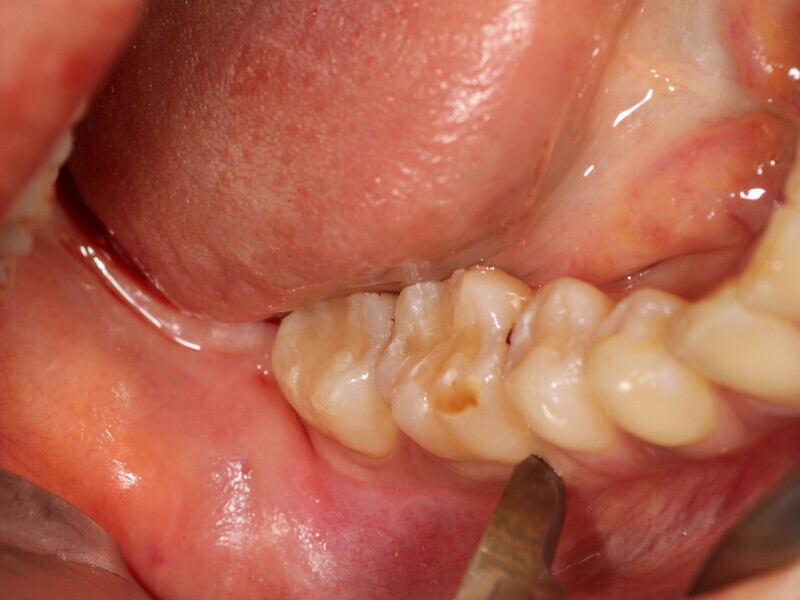

Fig. 6: A crestal incision is made with a sulcular incision to connect to the vertical releasing incision that was created then a full thickness flap is elevated to expose the lateral aspect of the mandibular body that will serve as the donor harvesting site.